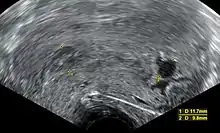

Transvaginal ultrasonography, with some products of conception in the cervix (to the left in the image) and remnants of a gestational sac by the fundus (to the right in the image), indicating an incomplete miscarriage

An incomplete miscarriage occurs when some products of conception have been passed, but some remains inside the uterus.[96] However, an increased distance between the uterine walls on transvaginal ultrasonography may also simply be an increased endometrial thickness and/or a polyp. The use of a Doppler ultrasound may be better in confirming the presence of significant retained products of conception in the uterine cavity.[97] In cases of uncertainty, ectopic pregnancy must be excluded using techniques like serial beta-hCG measurements.[97]